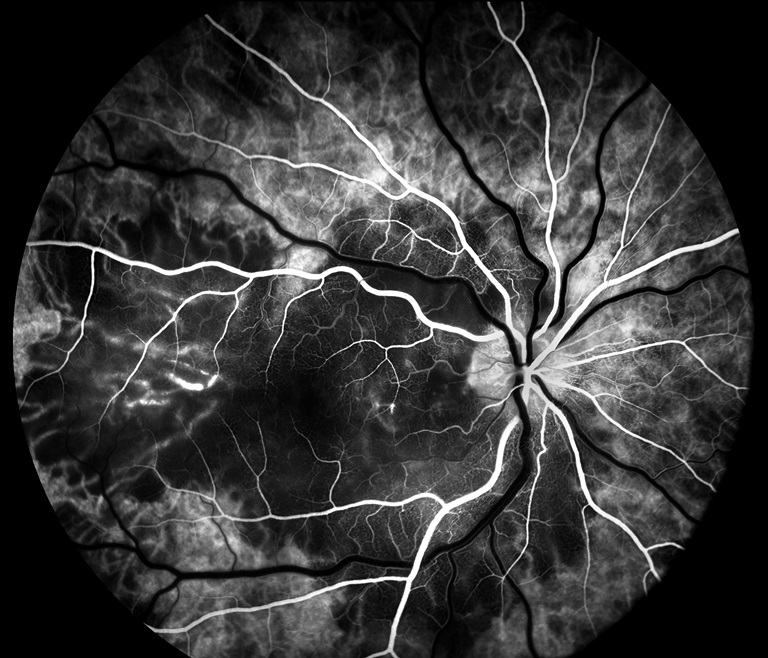

Apmppe

Presented by Meghan Menzel, BA, CRAThis photograph received 3rd Place in the category "Retinal Fluorescein Angiography" and was displayed at the 2024 ASCRS/OPS Society Exhibit.